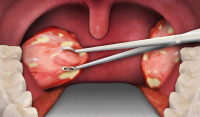

60 секунд щоб урятувати життя! Раннє виявлення раку ротової порожнини.

Хоча рак ротової порожнини - це візуальна форма раку, але у 70-80% його виявляють на ІІІ-IV стадіях захворювання.

Смертність протягом 1 року з моменту виявлення поступається місцем лише таким важкодоступним та дороговартісним для діагностики локалізаціям злоякісних новоутворень як рак печінки, рак підшлункової, рак мозку, шлунку, стравоходу.

Регулярні обстеження, тобто, скринінг слизової оболонки рота є важливим кроком для раннього виявлення хвороби, таким чином підвищується успішність лікування до 90%.